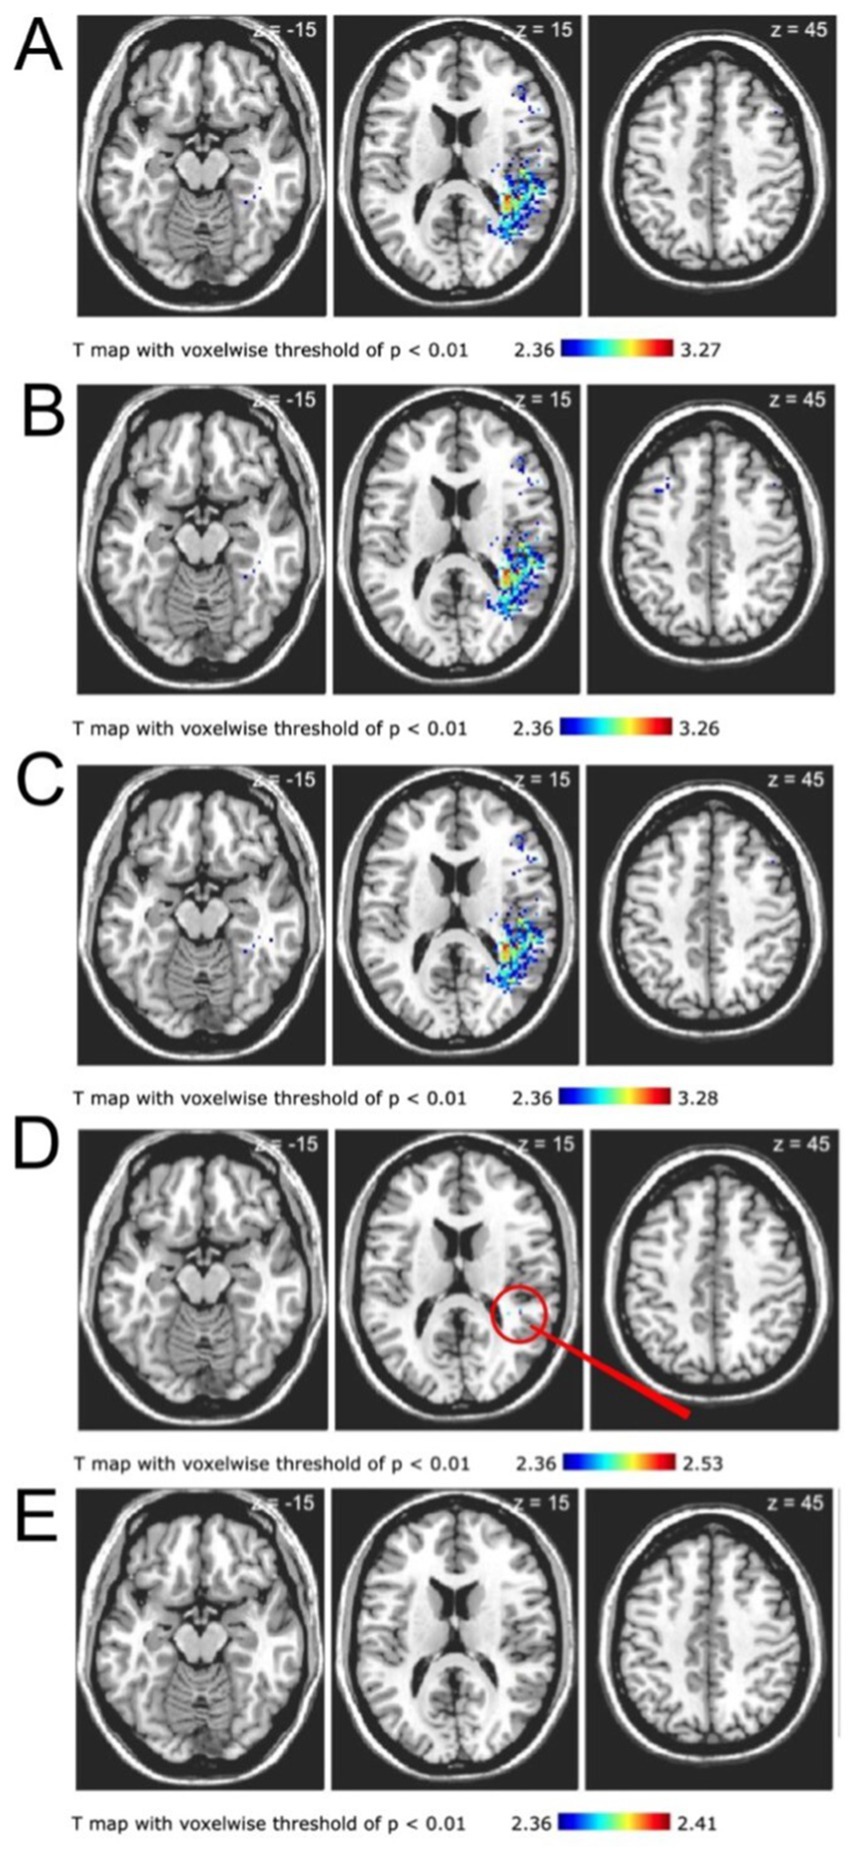

Voxel-based lesion symptom maps were generated using all post-stroke DWI lesions from 130 PEG cases and matched controls. Clusters of voxels, thresholded to a t-statistic of <0.01, in the right frontal, temporal and parietal lobes were associated with need for post-stroke PEG placement (Figure 1, panel A). After controlling for patient age there remained a similar relationship between right parietal infarct and PEG placement (Figure 1, panel B). Lesion symptom maps were also similar after controlling for recanalization status (in patients who underwent EVT, defined as Thrombolysis in Cerebral Infarction score) (Figure 1, panel C). However, after controlling for lesion size, only two punctate areas in the right parietal lobe were associated with PEG placement (Figure 1, panel D). Once all covariates were controlled for together (age, lesion size, and recanalization status), there was no topographic region that was associated with need for PEG placement in patients with LVO stroke (Figure 1, panel E).

Figure 1. Neuroanatomic regions associated with need for post-stroke PEG placement. All images are T-maps with voxel threshold of p < 0.01 derived from post-stroke DWI sequences. Lesion maps are in neuroanatomic (not radiologic) space; statistically significant voxels are in the right hemisphere. (A) T-map depicts voxels in right parietal, frontal, and temporal regions associated with PEG placement. (B) T map after correcting for patient age depicts right parietal, frontal, and temporal regions associated with PEG placement. (C) T-map after correcting for recanalization status depicts voxels in right parietal, right frontal, and right temporal regions associated with PEG placement. (D) T-map after correcting for lesion volume depicts only two punctate areas of the right parietal lobe associated with PEG placement. Red arrow marks the regions of interest. (E) T-map after correcting for all variables (age, recanalization, and lesion size) shows no region associated with PEG placement. The differences between A, B, and D compared with C and E demonstrate the importance of lesion volume in the need for post-stroke PEG placement.